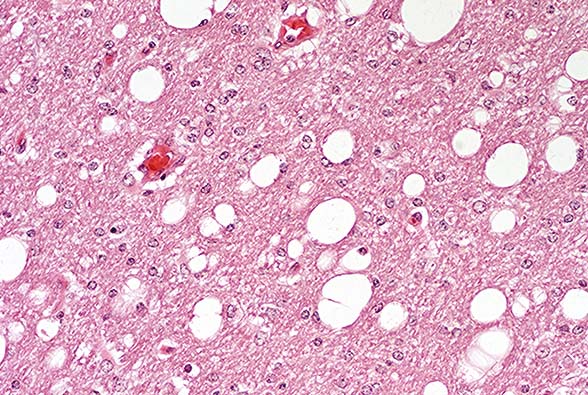

Case 14-3a. Cerebrum. Shows a nest of multinucleated cells in the deep cortex. 40X

Case 14-3b. Cerebrum. Demonstrates variably sized vacuoles in the neuropil. 20X